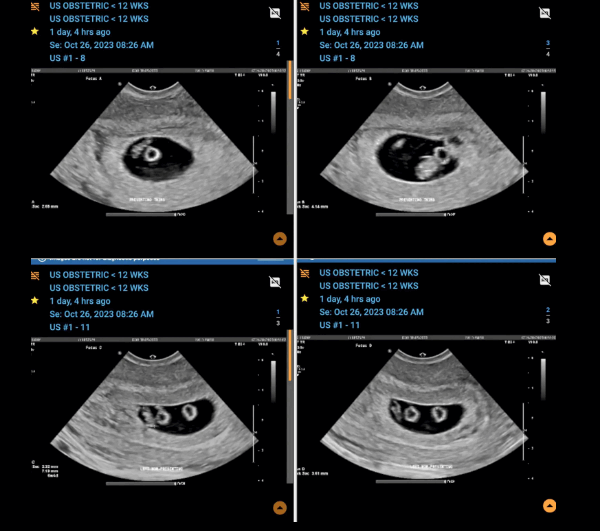

حملها يعتبر معجزة تحصل مرة من أصل كل 70 مليون حالة... 'أنا أم للمرة الأولى وأنتظر مجموعتين من التوائم المتماثلة'!

حملها يعتبر معجزة تحصل مرة من أصل كل 70 مليون حالة... 'أنا أم للمرة الأولى وأنتظر مجموعتين من التوائم المتماثلة'!